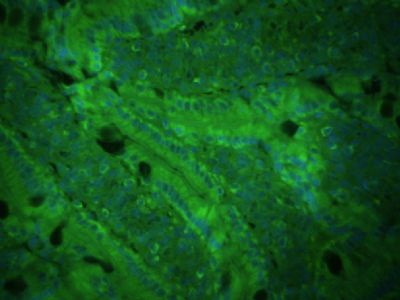

| 产品图片 |  Sample: BV2 Cell (Mouse) Lysate at 40 ug Primary: Anti- CXCL16 (bs-1441R) at 1/300 dilution Secondary: IRDye800CW Goat Anti-Rabbit IgG at 1/20000 dilution Predicted band size: 27 kD Observed band size: 27 kD  Tissue/cell: human lung carcinoma; 4% Paraformaldehyde-fixed and paraffin-embedded; Antigen retrieval: citrate buffer ( 0.01M, pH 6.0 ), Boiling bathing for 15min; Block endogenous peroxidase by 3% Hydrogen peroxide for 30min; Blocking buffer (normal goat serum,C-0005) at 37℃ for 20 min; Incubation: Anti-CXCL16 Polyclonal Antibody, Unconjugated(bs-1441R) 1:200, overnight at 4°C, followed by conjugation to the secondary antibody(SP-0023) and DAB(C-0010) staining  Images kindly provided by Dr. Denny Cottle from the publication, Fetal inhibition of inflammation improves disease phenotypes in Harlequin Ichthyosis.Formalin-fixed and paraffin embedded mouse skin probed with Rabbit Anti-CXCL16 Polyclonal Antibody (bs-1441R) at 1:50 for two hours at room temperature (green channel).  Paraformaldehyde-fixed, paraffin embedded (Rat colon); Antigen retrieval by boiling in sodium citrate buffer (pH6.0) for 15min; Block endogenous peroxidase by 3% hydrogen peroxide for 20 minutes; Blocking buffer (normal goat serum) at 37°C for 30min; Incubation: Anti-CXCL16 Antibody, conjugated (bs-1441R-AF488) at 1:100 overnight at 4°C; DAPI (5ug/ml, blue, C-0033) was used to stain the cell nuclei.  Blank control: A431. Primary Antibody (green line): Rabbit Anti-CXCL16 antibody (bs-1441R) Dilution: 3μg /10^6 cells; Isotype Control Antibody (orange line): Rabbit IgG . Secondary Antibody: Goat anti-rabbit IgG-AF647 Dilution: 3μg /test. Protocol The cells were incubated in 5%BSA to block non-specific protein-protein interactions for 30 min at at room temperature .Cells stained with Primary Antibody for 30 min at room temperature. The secondary antibody used for 40 min at room temperature. Acquisition of 20,000 events was performed. |